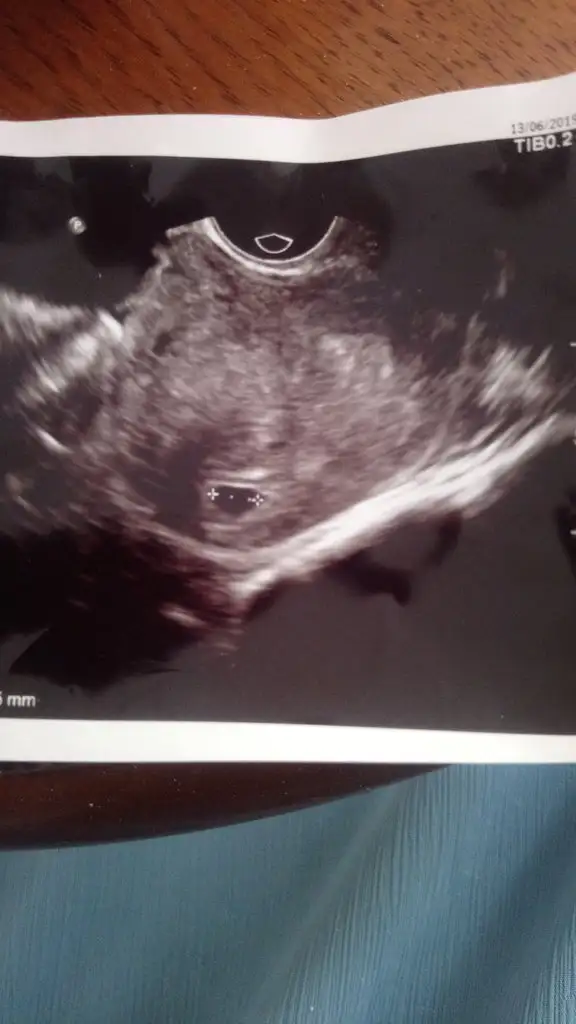

Bunu dün aldım, aslında giderken neredeyse 6 haftalık olmuştur kalbini duyabilirim diye gittim ama 4 yada 4,5 haftalık dedi doktor. Sat 11 Mayıs ve 10 Haziran'da hcg 741 çıkmıştı. Doktor üstten keseyi tam göremediği için alttan baktı ve bunu gördü sadece kalp atışını duyarız belki dedi ama kese içinde birşey görememiş çok mutsuzum şu anda. Birde ilaç kullaniyordum gyno lomexin akıntı vardı ve kaşıntı doktor fazla etki etmez ama ben olsam bunu vermezdim bebek düşünen birine dedi aklım çok karışık bel ağrısından ölüyorum. Doktora söyleyemedim bile ağrımi öyle küçük çıkınca.

Üzülme kuzum bende 5hafta 2 günlük gittim aynı bu şekilde sadece kese gördüm ve alttan aynı seninki gibi bana da kese kenarda dedi içe doğru büyümesi gerekiyor dedi...yarın doktora gidecem 6hafta 2günlük oluyor bakalım ben görebilecek miyim...bak benimde ultrason görüntün bu şekilde seninkine çok benziyor..Eki Görüntüle 2280346